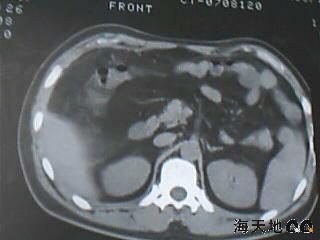

男 32y 外伤后一月余,现 t38.5,肝区隐痛。

右肝膈顶区液气平面.右膈肌增厚改变,病灶下部层面呈半月形延伸于肝表面.且于横结肠无明确密度切关系.

结合临床症状;考虑膈下脓肿.建议薄层矢状重建进一步证实.

鉴别;1,膈疝;2,间位结肠.

考虑右膈下脓肿。病灶不在肝内,位于肝外膈下;病灶下方的层面无结肠影与之相连。

右膈肌增厚,肝膈间见条状低密度影内可见积气影及宽大液平面,并未见与结肠相连。因此考虑膈下脓肿。